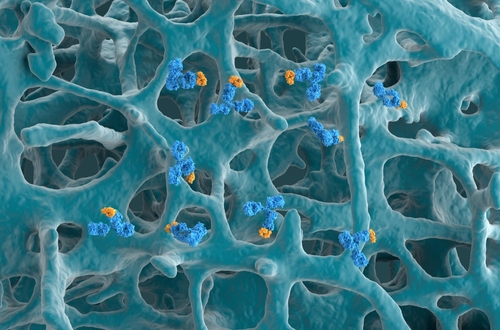

Citing the emerging evidence that thymic stromal lymphopoietin (TSLP) plays a key role in the pathogenesis of asthma in adults, researchers sought to establish its clinical relevance in children with asthma. According to their study, published in Frontiers in Pediatrics, higher baseline levels of pulmonary TSLP were linked to the severity of asthma in a subset of children.

The trial enrolled 35 asthmatic children (median years of age, 9) who underwent bronchoscopy and had bronchoalveolar lavage (BAL) samples evaluated for protein levels of TSLP, interleukin (IL)-5, IL-1β, and IL-33 at baseline. Parameters were then assessed against individual disease severity and clinical factors including spirometry, serum immunoglobulin E, and eosinophils, BAL neutrophil, and BAL eosinophil counts.

Compared to pediatric patients with mild or moderate asthma, those with severe asthma had higher median levels of TSLP (0.409 vs 0.923 pg/mL; P=.016) and IL-5 (0.248 vs 0.940 pg/mL; P=.016) in BAL at baseline. The authors noted that patients with severe asthma also had increased median levels of IL-33, but the difference was not statistically significant (78.88 vs 262.14 pg/mL; P=.088). Additionally, patients above the 75th percentile for TSLP levels had higher IL-5 and IL-1β levels in BAL, as well as a higher proportion of lower airway obstruction (P=.019).

The article summarized that the study demonstrated, for the first time, that baseline TSLP levels are associated with asthma severity in pediatric patients. “Given that pediatric asthma is major health problem worldwide, we feel larger longitudinal studies are urgently needed to define additional features of TSLP production in the lungs of asthmatic children,” the authors ended.